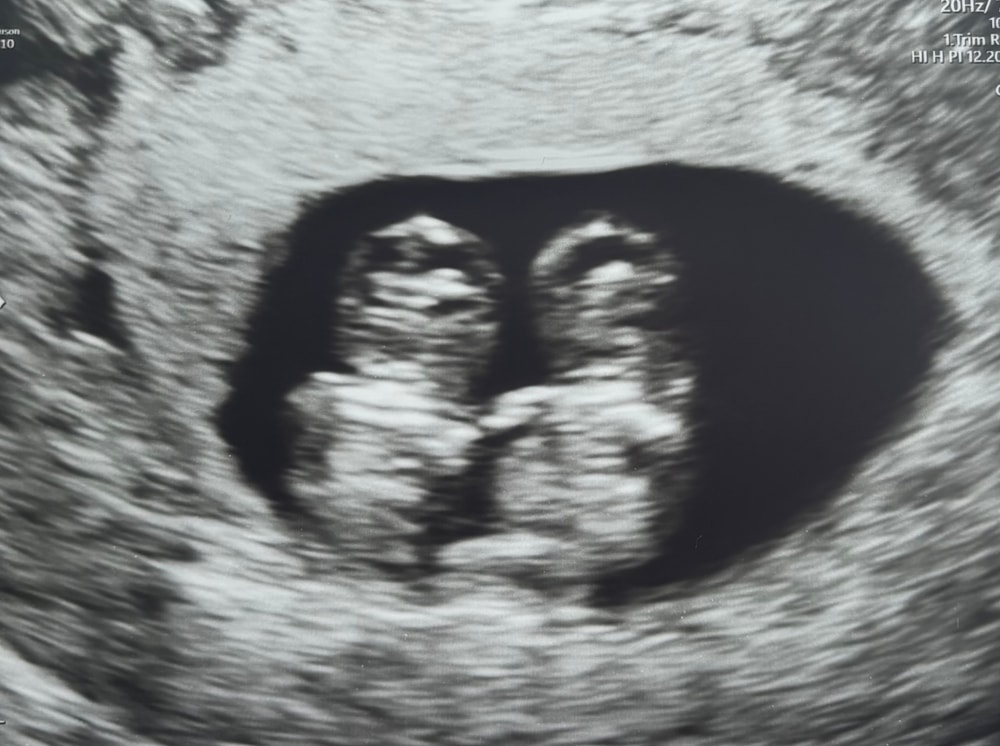

Теперь это моё любимое фото, врач сказал, что в этот момент вы держались за ручки ❤️

Решаю через 5 дней опять идти на узи, следить за ростом эмбриона. Врач начинает смотреть, я волнуюсь, думаю ну всё, наверное что-то случилось и тут она говорит: «я вас сейчас удивлю, но у вас тут их двое». Что??? Как??? Я была в шоке, муж был в шоке.

КТР у каждого малыша по 12 мм